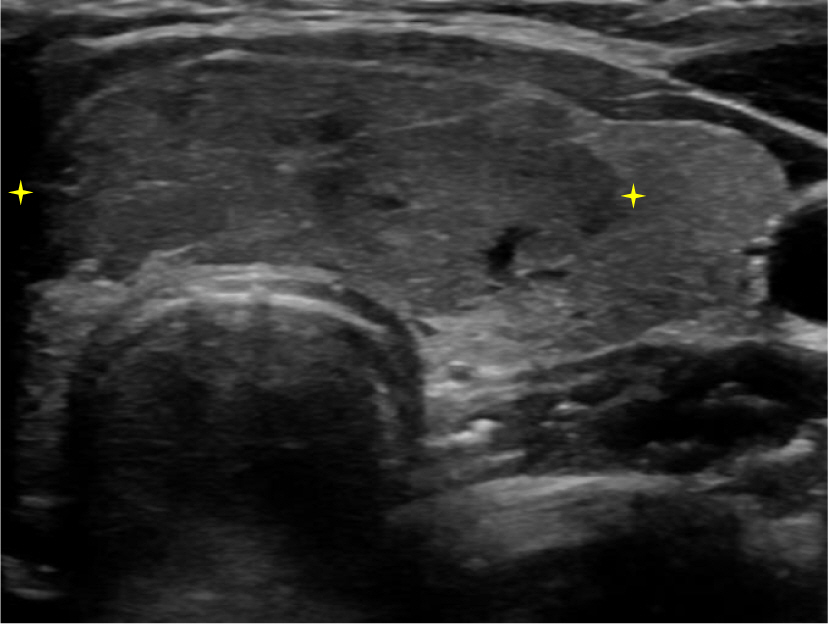

A 24-year-old female patient presented to Ewha University Medical Center in August 2021 with a palpable mass in the anterior neck. Upon examination, a movable mass measuring 2.5 cm was detected in the thyroid gland's isthmus. Thyroid function tests were within normal limits, with free thyroxine at 1.23 ng/dL and thyroid-stimulating hormone at 2.50 mIU/L. Ultrasonography of the thyroid revealed a hypoechoic nodule in the isthmus, measuring 3.1×1.1 cm (Fig. 1). A fine needle aspiration biopsy was performed, confirming the diagnosis of PTC (Bethesda category VI). The patient was informed of the test results and the implications of surgery. Opting to avoid a visible scar from an open procedure, she chose BABA robotic thyroidectomy. Informed consent was obtained following a thorough discussion about the advantages and disadvantages of robotic thyroid surgery without division of the isthmus. The patient subsequently underwent BABA robotic total thyroidectomy with central compartment neck dissection for the treatment of isthmic PTC.

Fig. 1.

Thyroid ultrasonography of an isthmic tumor.

Fig. 1. Thyroid ultrasonography of an isthmic tumor.